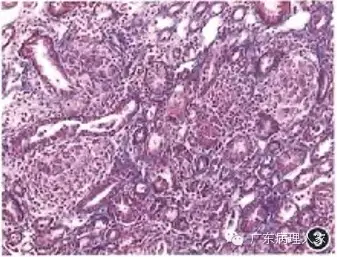

2.从事肾活检病理诊断的医师一定要具备全面的病理学基础。因为肾脏只是全身各系统的一个组成部分,肾脏疾病与其他器官的疾病密不可分,肾脏疾病常波及其他器官,同样,其他器官的疾病也常累及肾脏。如一个纵隔淋巴结肿大、肺内结节性病变的患者,出现肾功能损伤,肾活检病理显示为肾内多发性非干酪性上皮样结节,应诊断为肾的结节病(sarcoidosis),但有医院误诊为肾结核(图3),导致临床长时间抗结核治疗,以致丧失了对结节病的治疗机会,说明原病理医师的病理诊断的基本功较差。

图3 肾脏结节病,肾内多发性非干酪性上皮样结节 Masson法 中倍放大